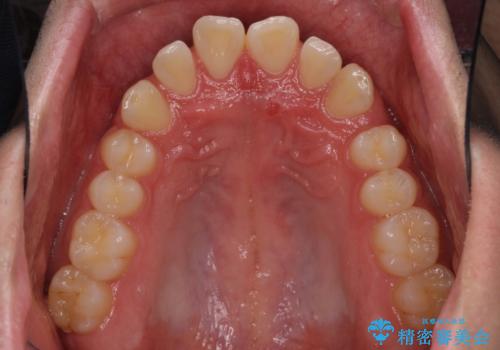

インビザラインによる、すきっ歯の改善

- 前歯がすきっ歯であることを気にして来院された患者様です。

下の前歯がほとんど隠れてしまうくらいの深い咬み合わせであったので、インビザラインを用いて、咬み合わせの高さを改善しながら隙間を閉じていくこととしました。

咬合力で上の前歯が前方に押し出されるようにして隙間ができていましたが、矯正治療により全て閉じることができました。

深い咬み合わせも多少改善され、隙間も閉じたことで、前方に出ていた前歯が引っ込んだため、口も閉じやすくなったとのことでした。